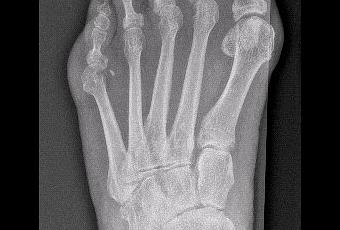

Esto hace muy difícil el calzado del pie y suele asociarse a mucho dolor por falta de espacio dentro del zapato, ya que la anchura del pie es mucho mayor a la normal.

Una vez agotados los tratamientos ortopédicos y de analgesia, se decide el tratamiento quirúrgico con la finalidad de alinear el pie corrigiendo las deformidades.

Estas técnicas a su vez se realizan mediante cirugía de mínima incisión, siendo el postoperatorio mucho más satisfactorio para el paciente.El resultado lo considero espectacular, no solo en la corrección de la deformidad, sino también en la obtención de un estrechamiento tranversal del pie de unos 2 cm (casi un 20% de su anchura), por lo que la paciente está ahora calzando zapatos normales sin ningun problema, cuando antes era imposible.Las radiografías de antes y después: